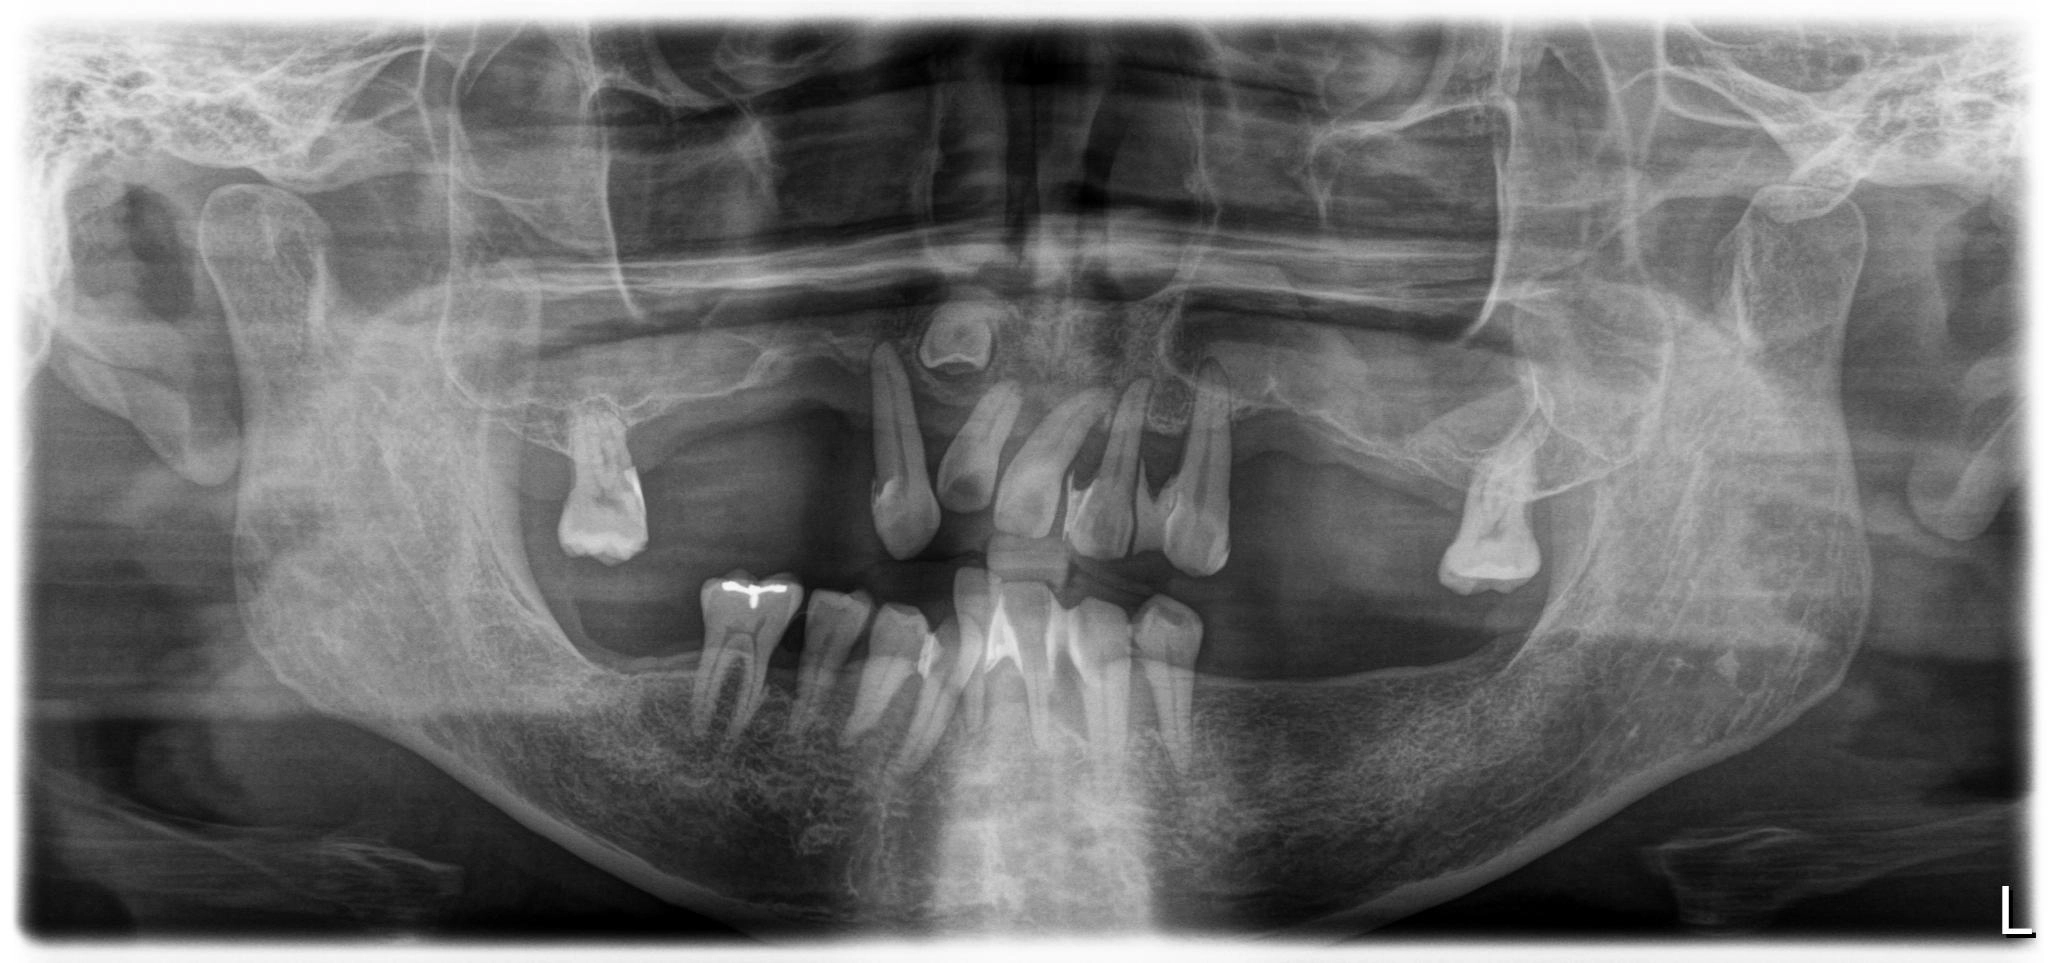

術前

内容 :上下顎オールオン4ザイゴマ4

費用 :5,500,000円

※モニター価格

期間 :半年

リスク:出血・腫れ・痺れ・痛み